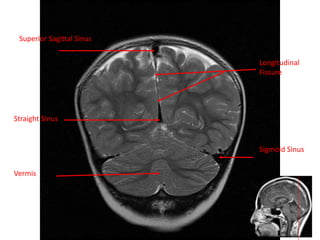

Longitudinal

Fissure

Straight Sinus

Superior Sagittal Sinus

Sigmoid Sinus

Vermis

• 61.